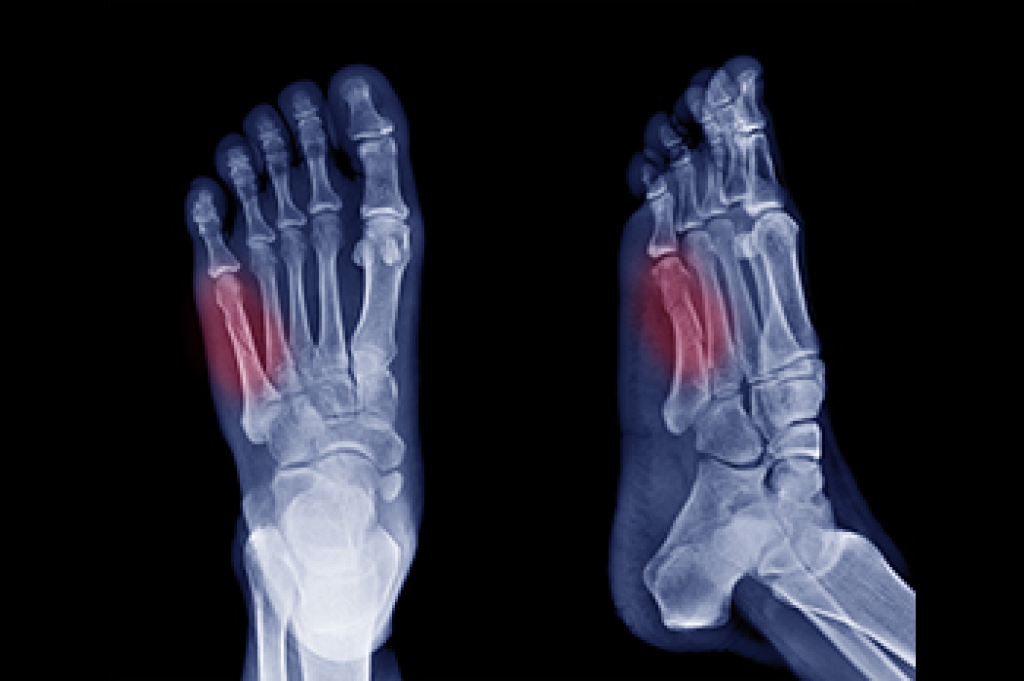

To treat neuropathy in the foot, podiatrists will first diagnose the cause of the neuropathy. Figuring out the underlying cause of the neuropathy will allow the podiatrist to prescribe the best treatment, whether it be caused by diabetes, toxic substance exposure, infection, etc. If the nerve has not died, then it’s possible that sensation may be able to return to the foot.

Pain medication may be issued for pain. Electrical nerve stimulation can be used to stimulate nerves. If the neuropathy is caused from pressure on the nerves, then surgery may be necessary.